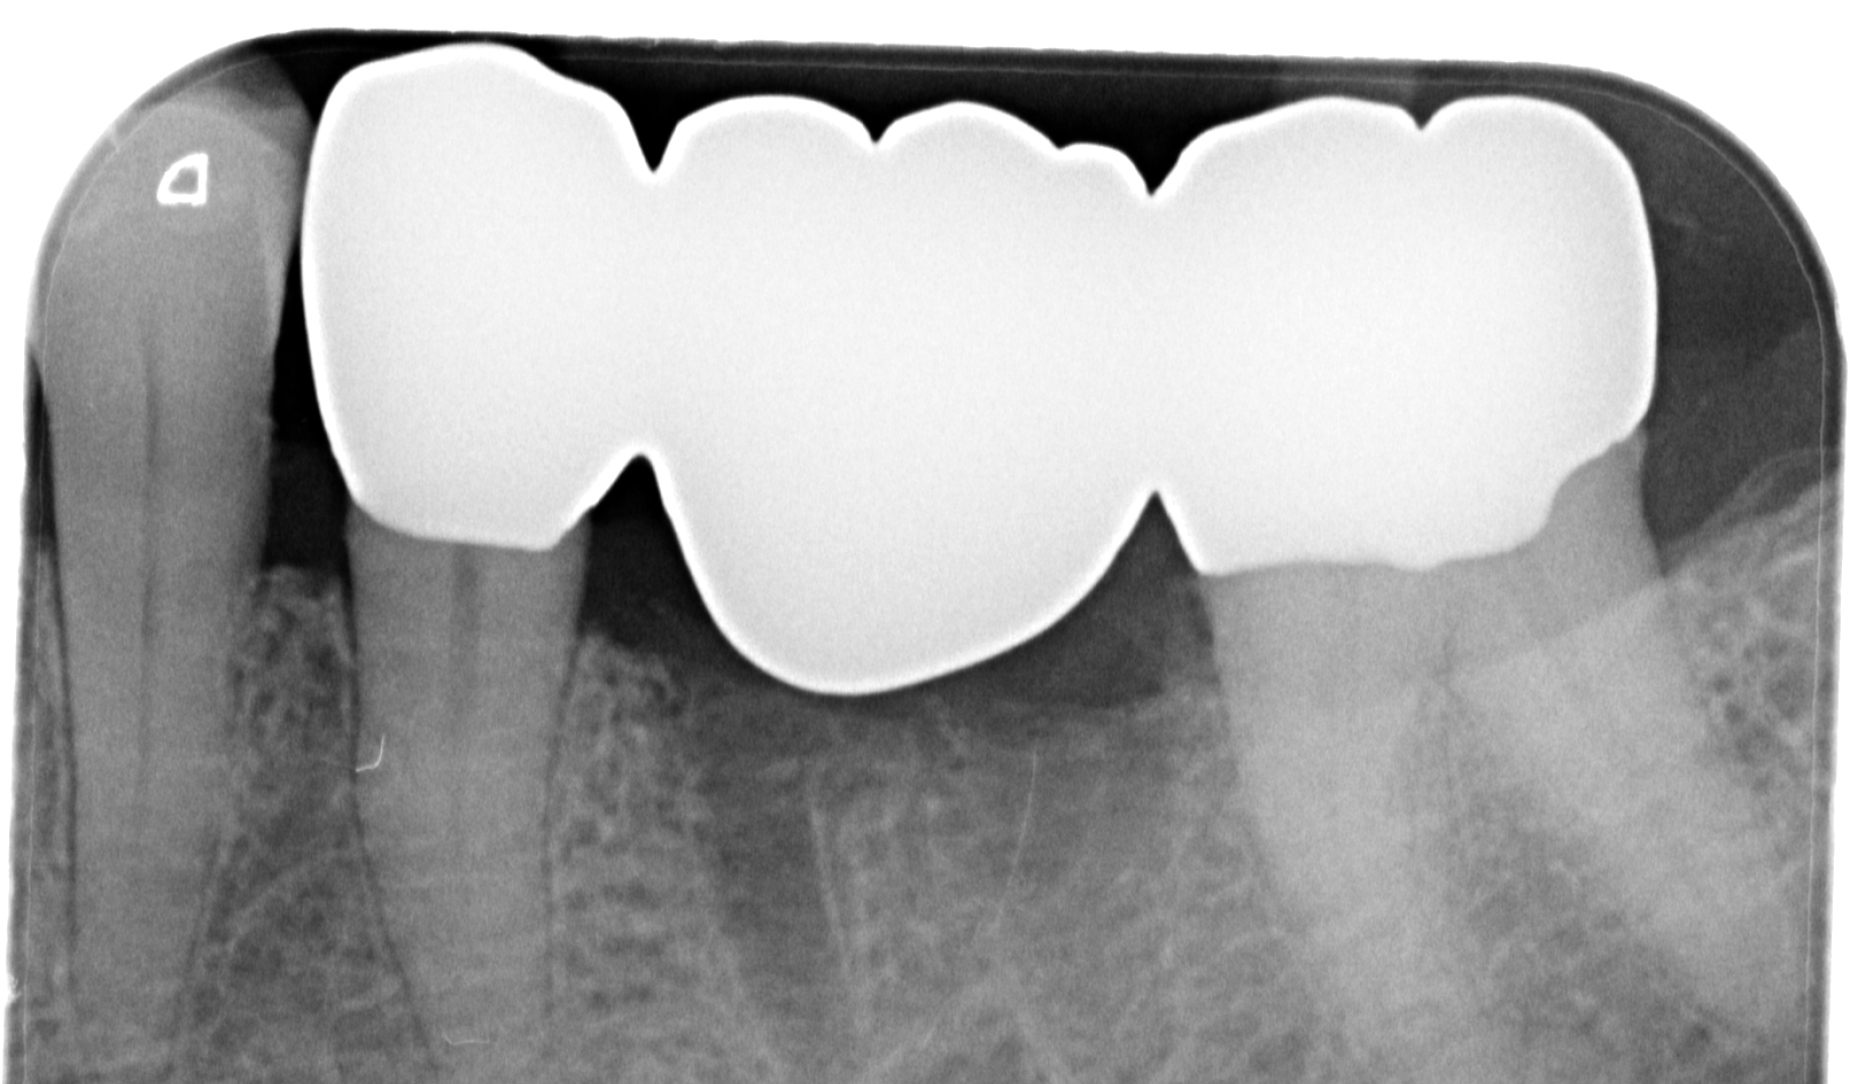

Ryc. 13. Kontrolne zdjęcie rentgenowskie, wykonane w celu sprawdzenia zalegania nadmiarów cementu wokół mostu.